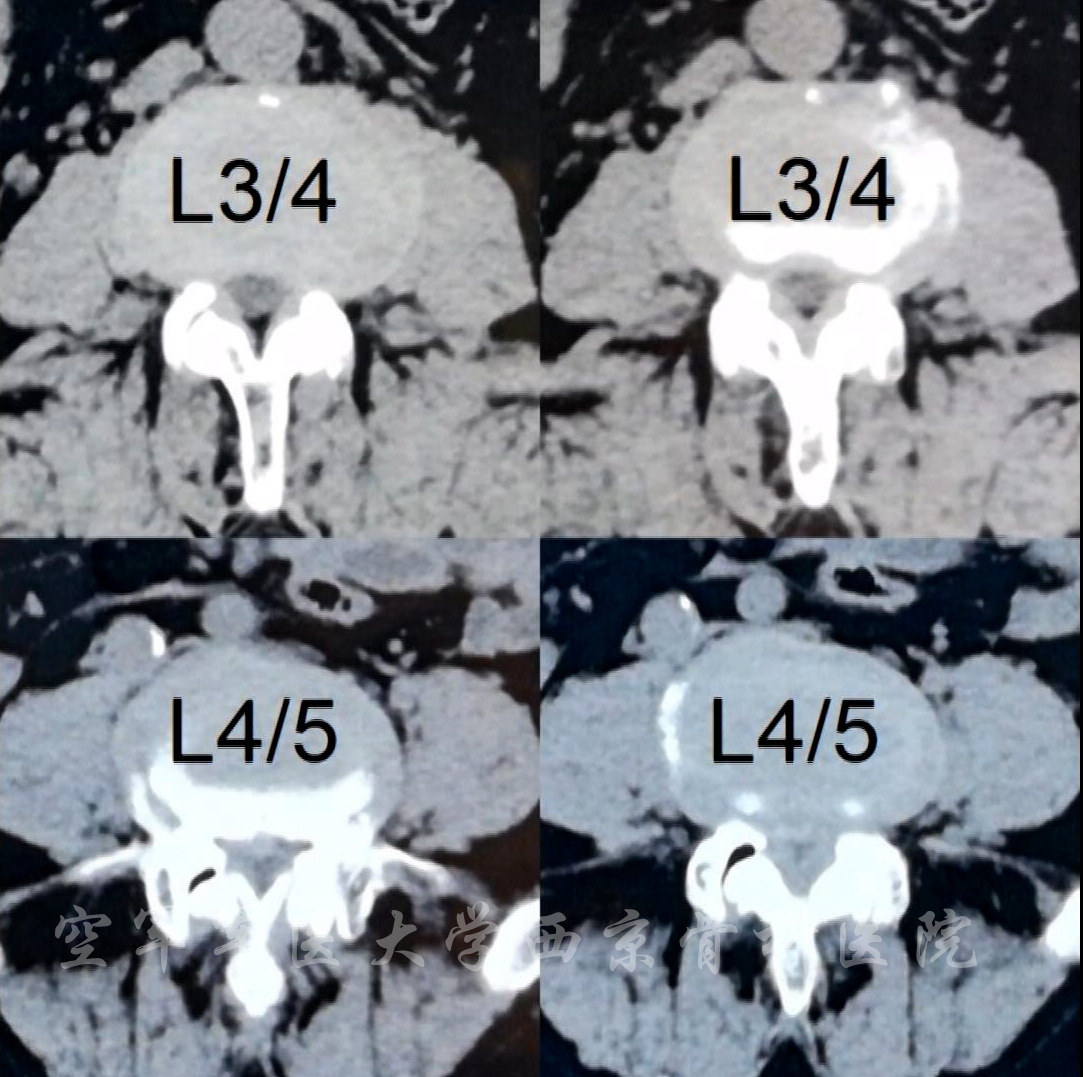

术前CT